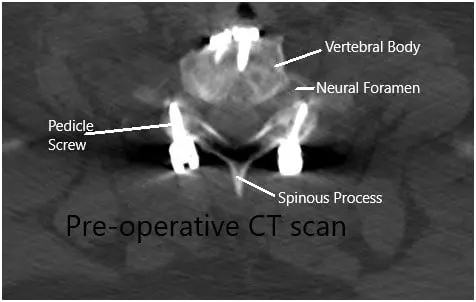

Imaging study revealed lateral disc herniations encroaching upon the neural foramen at C7-Tl and at Tl-T2, causing critical stenosis. Given his constellation of systems and weakness, we suspected also that he had a postfixed brachial plexus. obtained a thorough workup given the complexity of the patient’s imaging findings and clinical presentation and included MRI of the brain and brachial plexus.

Mild signal abnormality in the spinal cord at C5-6 of uncertain chronicity. At T1-T2 broad-based disc bulge with articular recess narrowing bilaterally. There were lateral disc herniations encroaching upon the neural foramen at C7-Tl and at Tl-T2, causing critical stenosis.

Preoperative CT scan in the axial section.